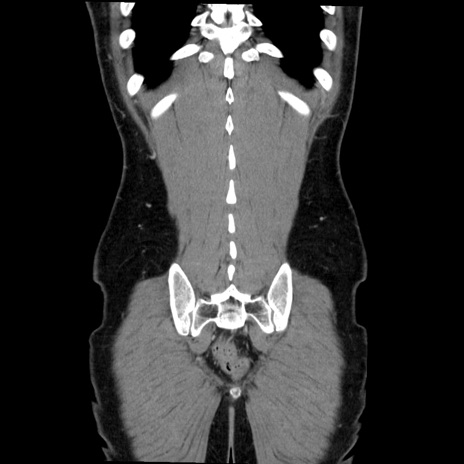

症例36(冠状断像)

【症例】20歳代 男性

【主訴】心窩部痛

【現病歴】今朝より上腹部痛あり。一旦軽快していたが再度出現したため救急要請。昨日夕に白身の魚を含む刺身を食べた。

【身体所見】BP 136/89mmHg、HR 74/min、BT 37.0℃、腹部:膨満、軟、心窩部に圧痛あり。反跳痛なし、筋性防御なし、腸雑音やや亢進あり。

【データ】WBC 17700、CRP 0.48